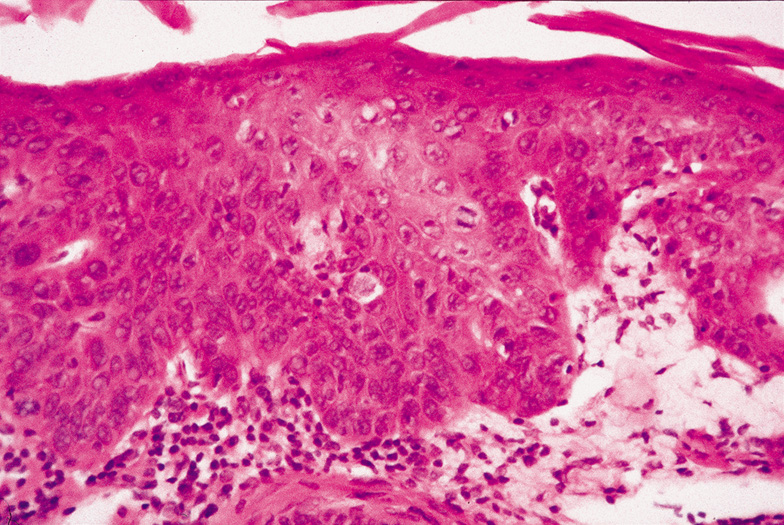

When epidermal atypia becomes full thickness, the clinical lesion is more indurated than actinic keratosis and becomes a plaque. Squamous cell carcinoma in situ may arise on sun-exposed skin from an actinic keratosis or de novo on sun-protected skin. The latter lesion is referred to as Bowen's disease. Squamous cell carcinoma in situ may enlarge slowly for many years or may invade the dermis.

Histologically, the epidermis is replaced by an atypical proliferation of keratinocytes showing nuclear hyperchromatism and pleomorphism. There are many dyskeratotic cells and mitotic figures, some of which may be atypical (Fig. 43). The overlying stratum corneum is parakeratotic. If occurring on sun-exposed skin, there will be solar elastosis.

Fig. 43. Carcinoma In Situ—A. Low-power photomicrograph demonstrating parakeratosis, hyperkeratosis, and epithelial dysplasia confined to the epithelium. No invasion is present. B. High-power photomicrograph revealing pleomorphic cells and active mitosis (hematoxylin and eosin stain). (Photos courtesy of William Morris, M.D.)